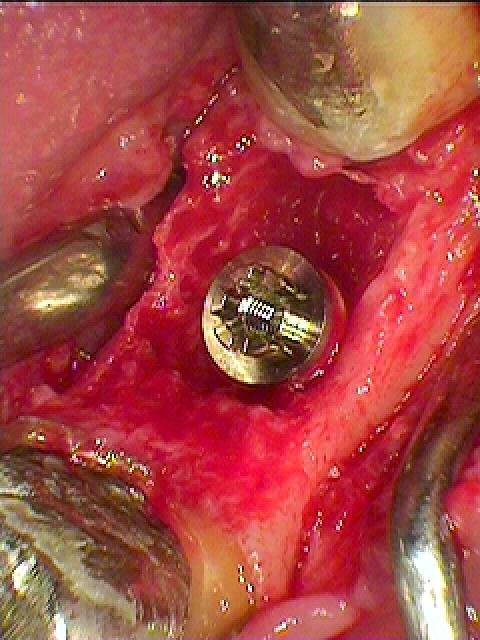

インプラント埋入になります

骨欠損が大きくGBRしていきます

下顎7番のインプラント埋入は下顎管とも近くなり、難しさはあります